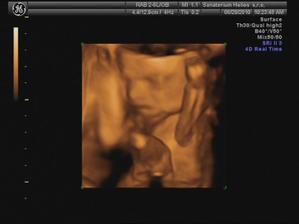

29.6. jdeme na 3D ultrazvuk 🙂 těšíme se... - bylo to úžasný 🙂 cena sice vyšší, ale jedna barevná fotka tištěná, 3 fotky na mail a téměř půlhodinové video, ze kterého jsme si doma udělali ještě asi 120 fotek 🙂